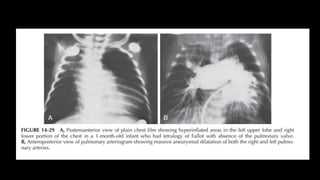

Tetralogy of Fallot with Absent Pulmonary Valve

Prevalence

Tetralogy of Fallot with an absent pulmonary valve

occurs in approximately 2% of patients

with TOF

Pathology and Pathophysiology

1. The pulmonary valve leaflets are either completely

absent or have an uneven rim of

rudimentary valve tissue present. The annulus of the

valve is stenotic and displaced

distally. A massive aneurysmal dilatation of the PAs is

present. This anomaly is usually

associated with a large VSD, similar to that seen in

TOF. It rarely occurs with an intact

ventricular septum.

4. Chest radiography shows a normal heart size. The heart often appears as a

boot-shaped silhouette (see Fig. 14-19), and the pulmonary vascularity is

usually markedly decreased (i.e., “black” lung field). Rarely, children with

MAPCAs have excessive PBF, and CHF may develop.